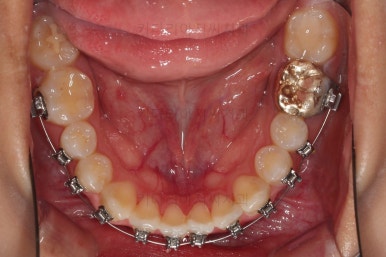

부산치아교정잘하는곳 키다리아저씨치과에서 사용한 장치는 엠파워라고 하는 자가결찰 장치인데요.

이번 환자분은 윗니는 세라믹, 아랫니는 메탈로 선택을 하셨습니다.

웃을 때 더 많이 보이는 부분은 좀 더 심미적인 세라믹으로 하고, 아랫니는 메탈도 상관없다고 하여 조합해서 사용했는데요.

동일한 회사의 동일한 규격의 장치라 혼용해서 써도 무방합니다.

장치 부착한지 얼마 안되어 치열은 매우 고르게 되었는데요.

치료 목표는 그것 뿐만 아니라 입을 조금이라도 넣고, 앞니 각도도 개선해야 되었으므로 사랑니는 모두 뽑아내고 미니스크류를 활용해서 뒤로 뒤로 밀어넣습니다.

특히나 주의행야 할 점은 주걱턱이신 분들은 아랫니를 뒤로 밀 때 그냥 밀면 안되고 뿌리까지 뒤로 같이 와야하는데요.

그래야 아랫입술의 변화가 드라마틱하게 됩니다.

해당 부분을 매우 신경써서 진행했습니다.